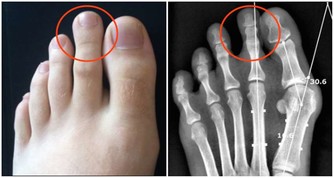

超聲科醫師檢查發現其右側陰囊空虛,右側腹股溝內可見大小約2*2*1cm的類睾丸迴聲,診斷考慮:隱睾症。

超聲科劉友員主任醫師解釋,“蛋蛋”不在陰囊裡就是俗稱的“隱睾症”。

隱睾,是指睾丸在正常發育過程中未下降或下降不全至陰囊,陰囊內沒有睾丸或只有一側有睾丸。

正常睾丸大小約4*3*2cm,位於陰囊內,

陰囊是最適合睾丸生長發育的場所,陰囊內溫度比體溫低1° C-2°C,有利於睾丸產生精子。

而隱睾患者睾丸未進入陰囊,長期留在腹腔和腹股溝管內,這些部分局部溫度高,

可導致睾丸生精細胞損害,影響精子的產生和生存,易導致不育。